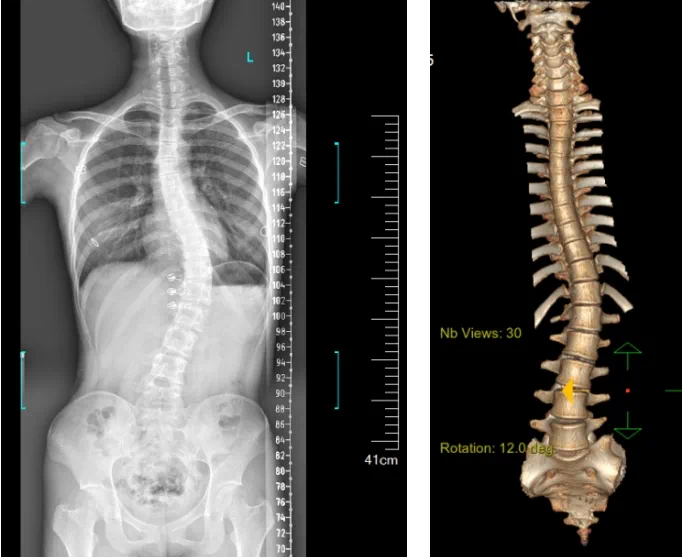

近日,南方醫院贛州醫院脊柱外科成功實施贛南首例機器人輔助下脊柱側彎矯形、植骨融合內固定術。

患者為一名16歲女孩,發現脊柱側彎1年,到南方醫院贛州醫院脊柱外科求診。經查體,患者左右胸廓不對稱,雙肩等高,左肩胛骨隆起,背側呈“剃刀背”畸形,胸腰段棘突偏離正中線,胸腰段脊柱左側凸畸形;各棘突無壓痛及叩擊痛,右側腰部凹陷,胸腹及腰背部感覺正常。檢查發現患者特發性脊柱側彎,Lenke5C型,主胸彎51°。患者及家屬對外觀不滿意,為改善外觀及功能,要求手術矯形治療。

在與患者及家屬充分溝通后,針對患者的病情,脊柱外科團隊在科主任陳榮春的指導下,經過術前仔細評估,制定了機器人輔助下脊柱側彎矯形、植骨融合內固定手術的治療方案,由郭朝陽主任醫師主刀實施。

據悉脊柱側彎手術治療后可以保持軀干平衡,改善外觀并防止畸形進一步發展。患者的生活質量得到提高,進而減少脊柱過度畸形可能帶來的疾病的發生率,外觀上的積極變化往往也能帶來患者心理與精神的積極變化。臨床上會綜合考慮患者的年齡、側彎程度、進展趨勢、骨質條件、鄰近節段情況、手術節段等因素,合理采用個性化的手術方式進行治療。然而,由于脊柱神經血管密布,手術操作相對復雜,手術難度高、風險大,傳統脊柱側彎的手術方式往往有較高的神經或脊髓損傷風險。故此次科室決定開展機器人輔助導航下脊柱側彎矯形、植骨融合內固定手術。術前,醫生團隊在機器人多維度圖像融合智能手術規劃功能的輔助下,預先規劃了理想的置釘路徑。術中,天璣骨科手術機器人準確遵循術前規劃,根據配準結果,實時定位并準確執行置釘操作,所有導針均用電鉆置入,一次性成功,協助醫生順利完成手術。最終,在麻醉科、手術室密切配合下,歷時3小時成功完成側彎矯形術,出血量僅500ml。術后,患者恢復良好,大小便及下肢神經運動感覺正常。

圖為置釘后